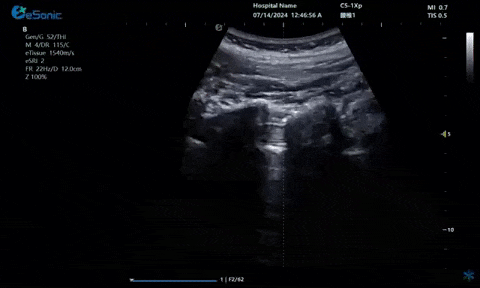

超声引导硬膜外麻醉-小等号

管内麻醉